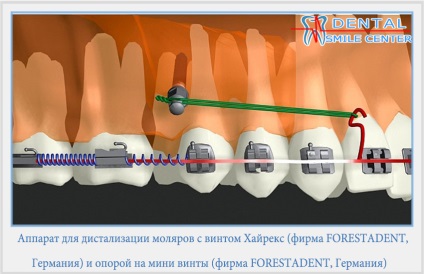

Distalization moláris - az az oldal csoport fogszabályozási mozgását a fogak (őrlőfogak) ezelőtt. Distalization őrlőfogak gyakran az első lépés a kezelésére különböző malocclusions eltávolítása nélkül a premolárisoknál vagy a kezelés a eltávolítása a második őrlőfogak. By eszközök distalization felső őrlő fogaknál levehető extra- és intraorális, például egy arc arc, a lemez csavarral és ágazati megszorítások, amelyek előírják jó együttműködés az orvos és a beteg nem eltávolítható eszközök.

Vannak különböző lehetőségek distalization az őrlőfogak, de az egyik leghatékonyabb megoldásnak - az, hogy egy fej tolóerő. Rögzítőgyűrűk folyik hat foga. Mivel a gyűrű két cső, fel tudjuk használni azokat más célra. Ha azt szeretnénk, hogy alakulat mozgás, akkor használja a cső, amely közelebb áll a központban az ellenállás a fogat. Ha kell kezelni tipilnye mozgás azt jelenti, használt cső, ami távolabb van a központtól az ellenállás. A fej tolóerő alkalmazott a fejlődő szervezetben.

Felnőtt betegeknél az distalization zápfog a leggyakrabban használt mikro. A kapcsolási elrendezés microimplants distalization őrlőfogak részletes a „microimplants”.